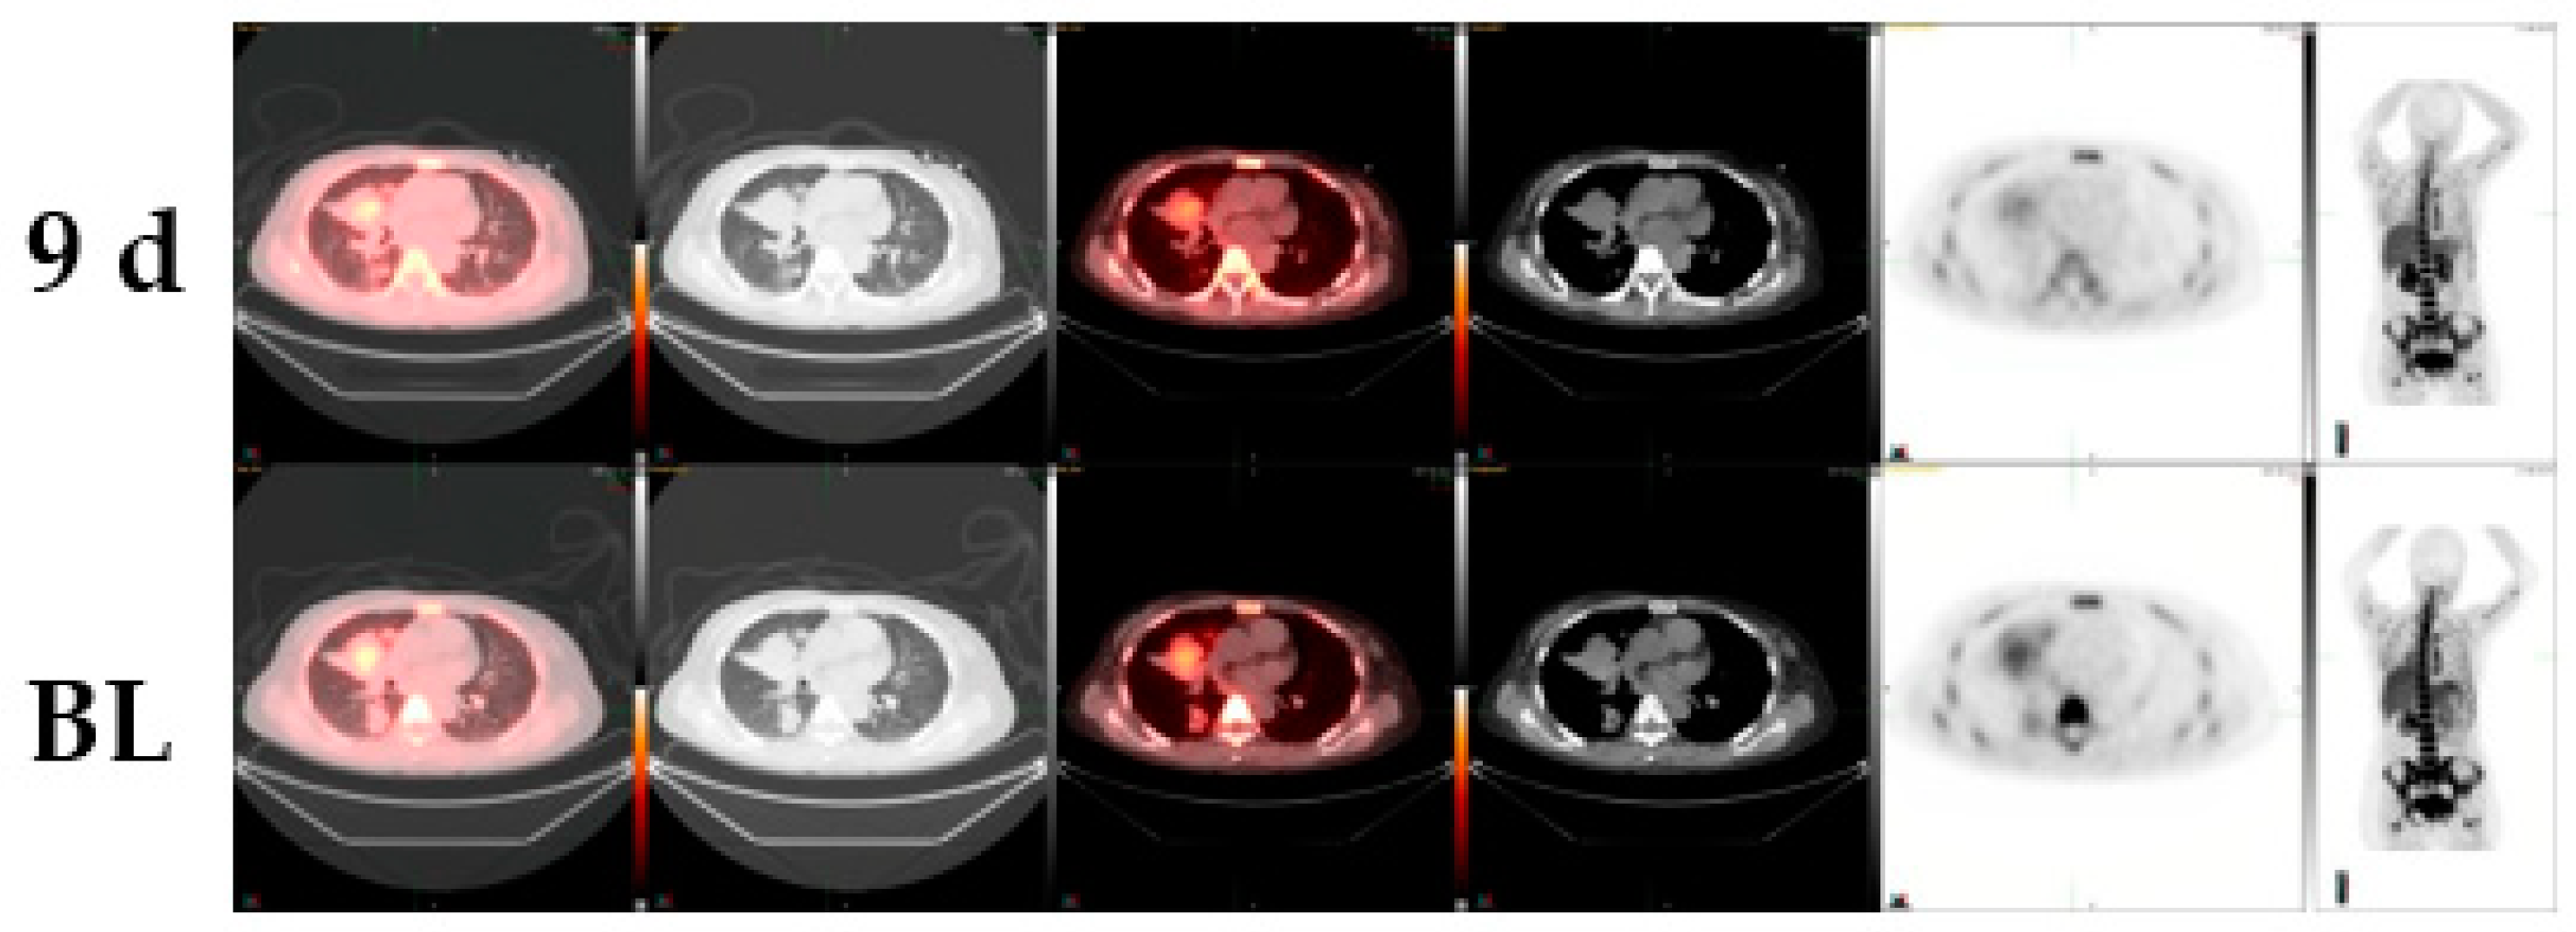

| 49/male c-MET-inhibitor | small cell lung cancer | cisplatin, etoposide | −38% | FDG-change +2% CT-change 0 % |

| 51/female c-MET-inhibitor | lung adenocarcinoma | erlotinib, carboplatin, gemcitabine/docetaxel, pemetrexed, sorafenib, irinotecan, bevacizumab | −24% | EGFR positive CT-change +2% |

| 59/female MDM2 inhibitor | lung adenocarcinoma | cisplatin, vinorelbine, pemetrexed, cetuximab | −31% | EGFR negative CT-change -6% |